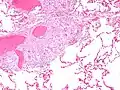

肺部病變是迄今為止最常見的結節病病理改變。約90%的患者在他們的患病過程中會出現胸部X線異常。總體而言,約50%患者出現長期的肺部異常,5%至15%有肺實質進行性纖維化。肺結節病主要是肺間質的炎性改變,涉及到肺泡、小支氣管和小血管。通常在急性和亞急性的情況下體檢會聽到肺部的幹性啰音。[20]

肉芽腫性炎症的特點是由單核細胞、巨噬細胞和活化的T-淋巴細胞參與,與增生的關鍵性炎症介質、IFN-α、IFN-γ與白細胞介素12、Th1-分化的細胞反應(輔助性T淋巴細胞反應)有關。結節病有著自相矛盾炎症過程的影響:其特征在於能激活巨噬細胞和T輔助細胞(CD4+),導致炎症反應加速,但免疫反應的抗原的具有反作用,如結核菌素被抑制。這種矛盾性作用不僅使反應活性增高而且同時也降低最後造成了一種無反應性(anergy)狀態。無反應性也可能使感染和得癌症的風險增加。調節性T-淋巴細胞中的外周性結節病中肉芽腫的出現抑制了IL-2的分泌,有人猜想其通過阻止抗原特異性記憶反應所導致的無反應性。[53]

肖曼小體中可以看到,在結節病中,鈣和蛋白質的混合物成為朗漢斯巨細胞肉芽腫內部的一部分。